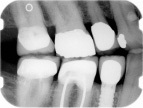

Radiographically, a dental implant looks like this:

Implant in bone Implant with crown attached